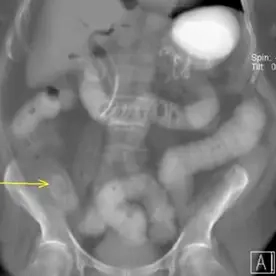

Die abdominale CT bestätigt den bereits klinisch geäußerten Verdacht auf einen Gallensteinileus. Es besteht ein mechanischer Dünndarmileus durch den obstruierenden großen Gallenstein prävalvulär an der Bauhin'schen Klappe sowie eine Aerobilie. Die Aerobilie kann sowohl durch die bereits durchgeführte ERCP mit Stentanlage als auch durch die Gallensteinpermeation bedingt sein.

Das Erscheinungsbild entspricht der Rigler-Trias und ist besser zu erkennen als im Röntgenbild. Da nur eine Minderheit der Gallensteine verkalken (12,5 %) und ihre Dichte dem normalen Darminhalt ähnelt, kann man den Gallenstein leicht übersehen. Kurz vor dem Übergang kann es zu einer Ausstülpung des Darms kommen, was bei der Lokalisierung des Gallensteins hilfreich sein kann. In der Regel sind die Steine groß und messen mehrere Zentimeter (2-3 cm).